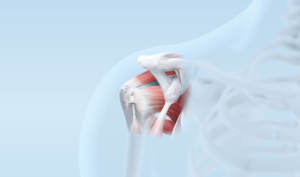

Rotatorenmanschette

Verletzungen der wichtigen Schultersehnen (Rotatorenmanschette) treten sehr häufig auf; durch den Funktionsverlust und schlafraubende Schmerzen in der Nacht wird die Lebensqualität erheblich beeinträchtigt.

Die Notwendigkeit und Machbarkeit einer Sehnenrekonstruktion werden in jedem individuellen Fall sorgfältig abgeklärt und abgewogen. Der Eingriff ist in den allermeisten Fällen in arthoskopischer Technik (Schlüssellochtechnik) ausführbar.

Neben der anspruchsvollen Operation erfordert insbesondere auch die erfolgreiche Nachbehandlung viel Erfahrung.